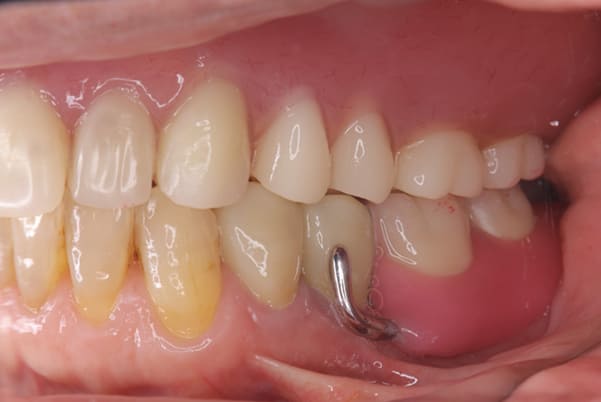

作製した入れ歯は、お食事の際に入れ歯の沈み込みを予防するため、適切なストッパーを付与することで、入れ歯は沈み込まなくなり、お痛みは消失しました。

右下のバネの位置は後ろに、左下のバネは見えづらい形態のバネを用いる設計とすることで笑った際にバネが見えないようになり、気にされることはなくなられました。

治療前後の口元の比較

こちらは、口を少し開いた時の治療前と治療後の

口元です。

正面から見た時にクラスプが目立たないように、

歯ぐきになじむ素材にて入れ歯を製作し、痛くなく自然に馴染み快適に生活を送れるようになりました。